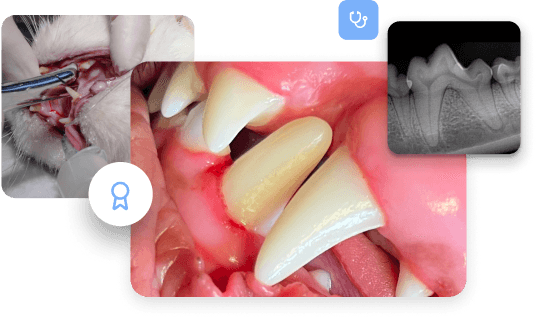

Auf Überweisungsbasis bietet sie eingehende Diagnostik, spezialisierte Chirurgie und begleitendes Fallmanagement für komplexe Zahn- und Kieferfälle bei Kleintieren.

Endodontie und Restauration

Wurzelkanalbehandlung, Vitalerhaltung der Pulpa, direkte und indirekte Restaurationen, Füllungstherapie, Rekonstruktion von Zahndefekten, Kariesbehandlung.

Mund-, Kiefer- und Gesichtschirurgie

Komplexe Zahnextraktionen, chirurgische Versorgung von Kieferfrakturen sowie Behandlung von Zysten, Fisteln und anderen oralen Läsionen. Weichgewebe- und Knochenchirurgie.

Kieferorthopädie und Kronen

Dentale Rekonstruktionen und Kronenversorgungen, funktionell und medizinisch indizierte kieferorthopädische Eingriffe.

Periodontologie

Geschlossene und offene Parodontaltherapie, regenerative Verfahren sowie Management fortgeschrittener Parodontitis mit Fokus auf Zahnerhalt.

Kompetenz bei komplexen Fällen

Kieferfrakturen, orale Tumoren und anspruchsvolle maxillofaziale Chirurgie.